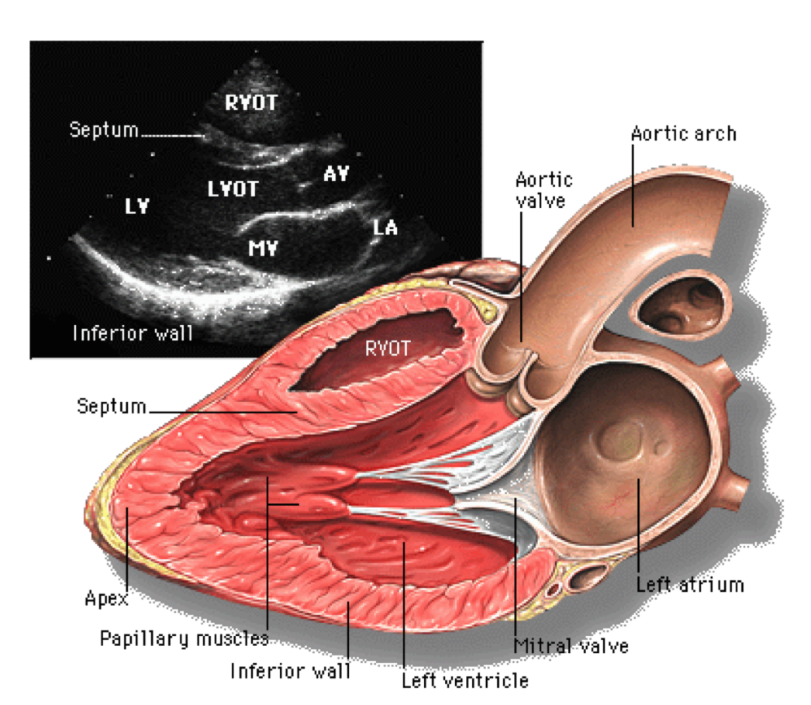

• Cardiac Echocardiography: Basics and Uses

• Anatomy and Physiology of the Heart